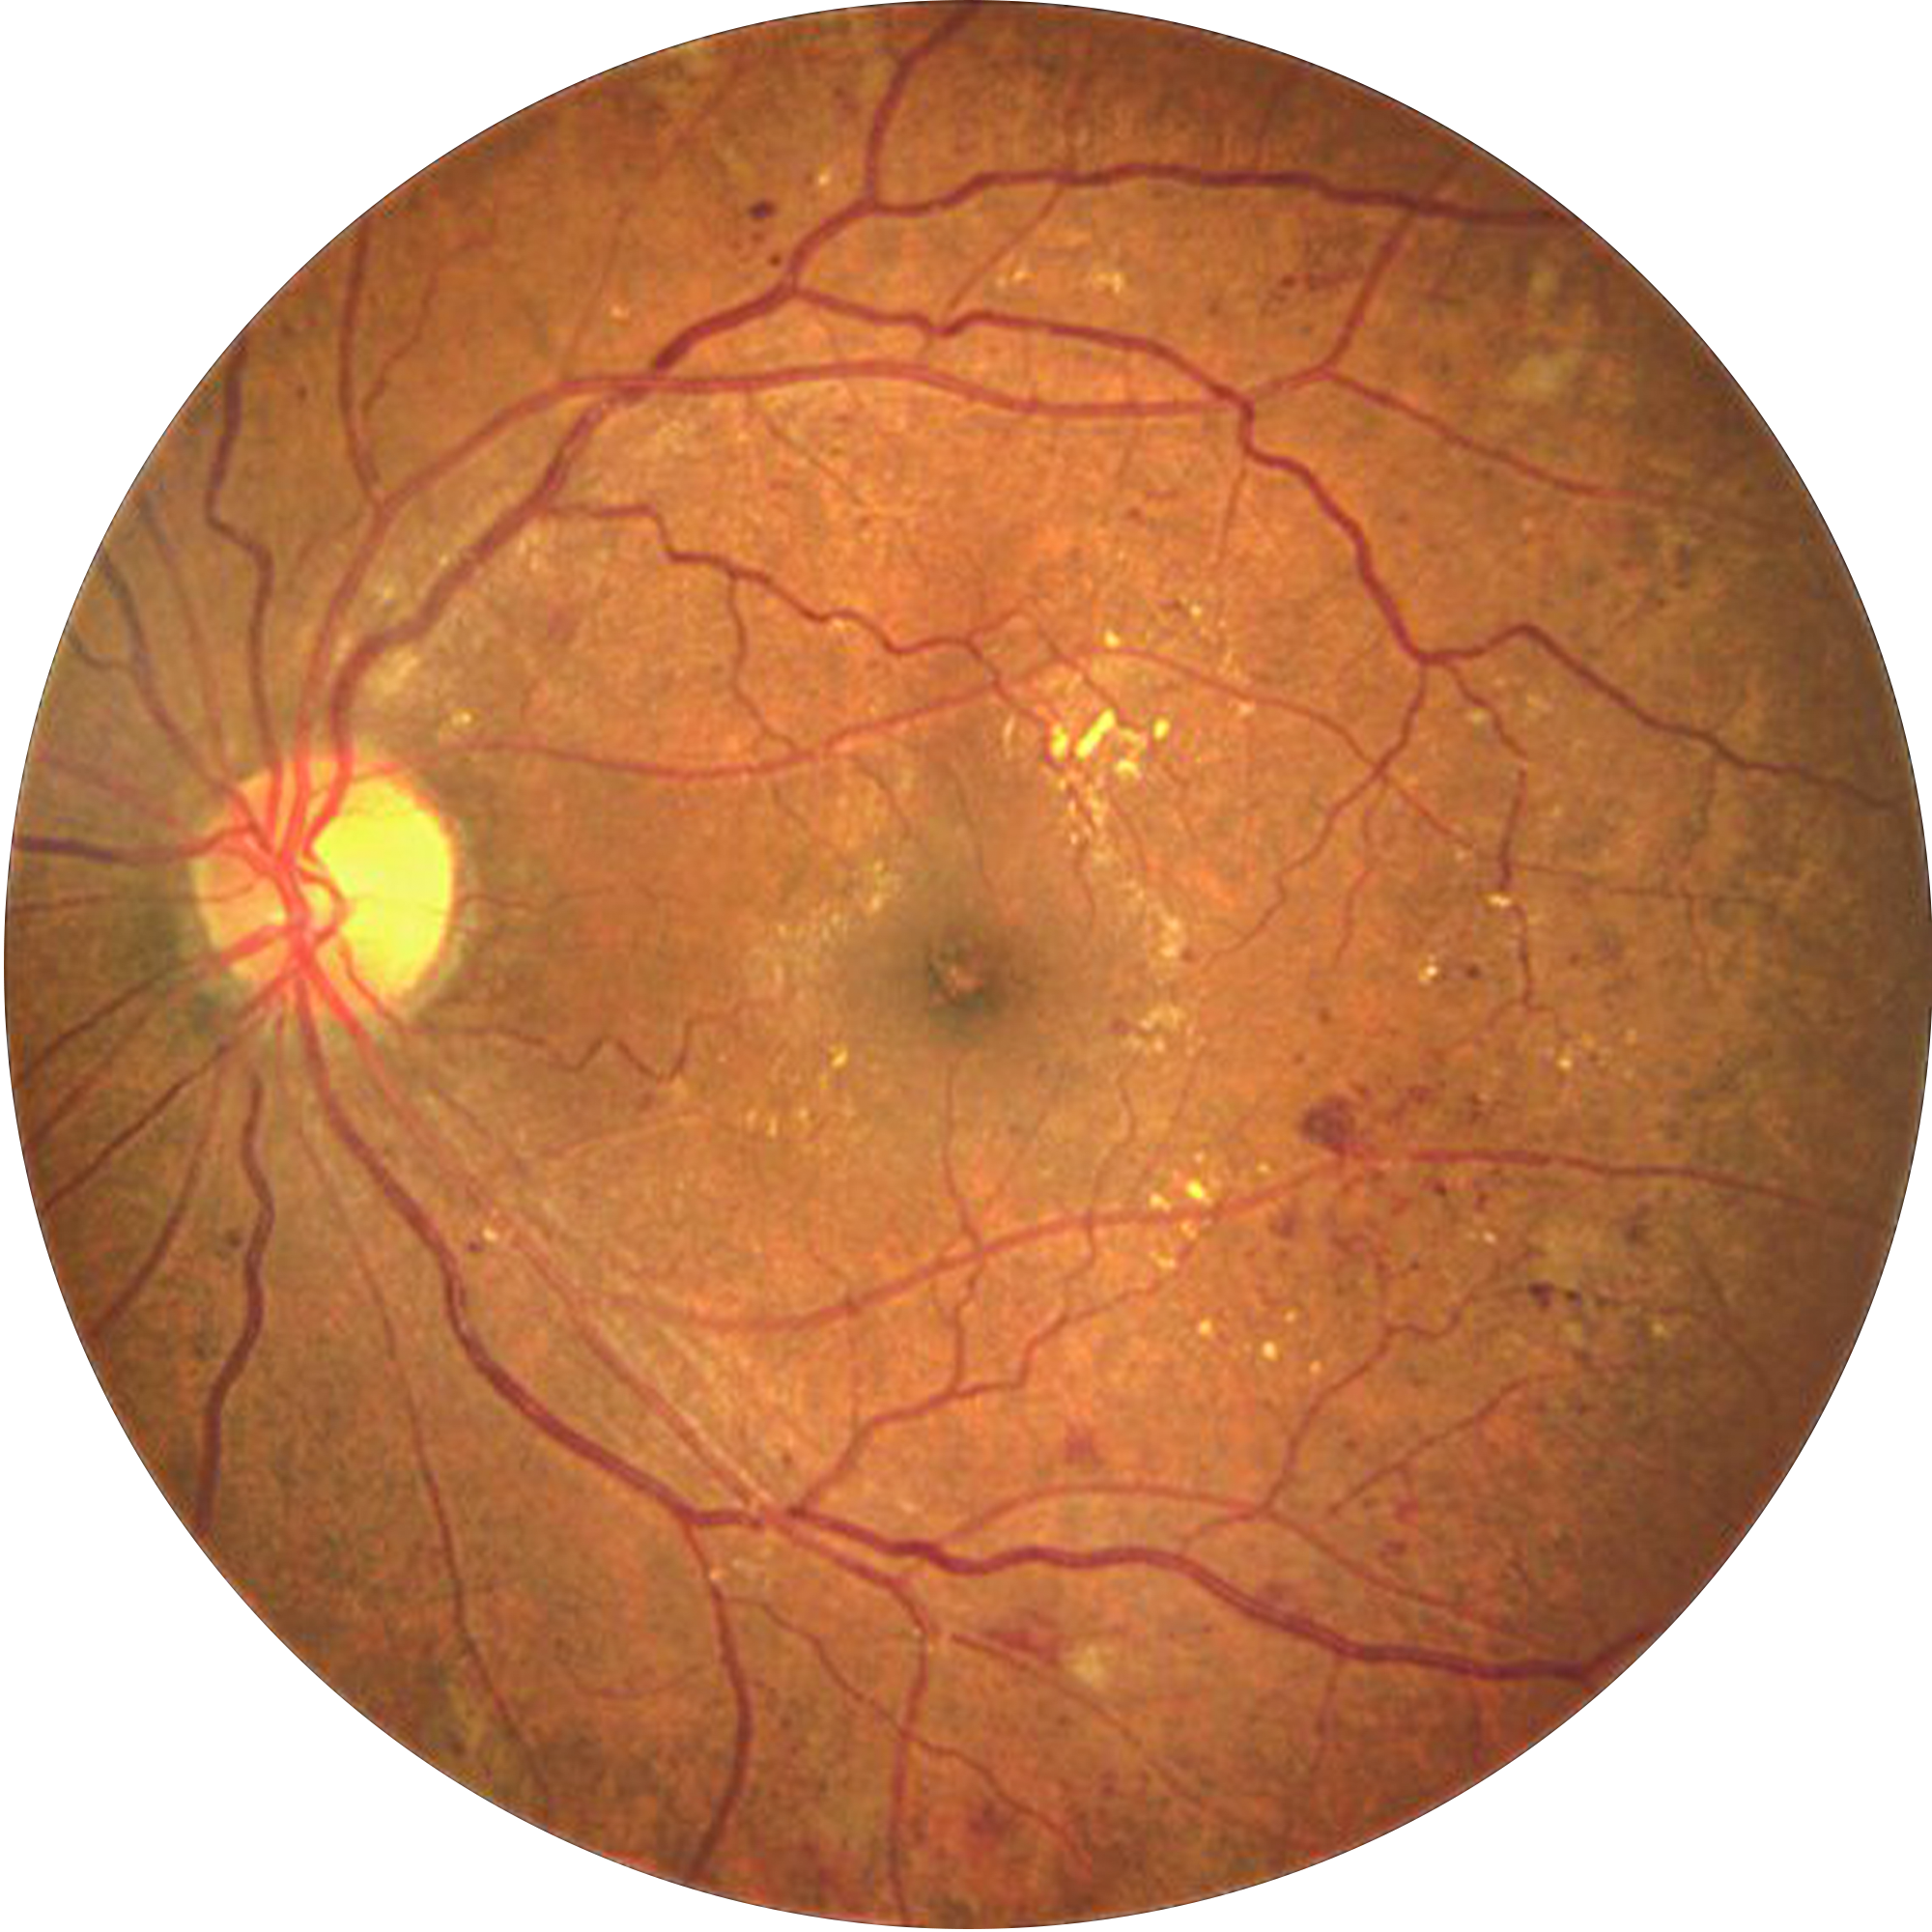

Designed to support retinal imaging in eyes with mild to moderate media opacity help maintaining reliable image quality during screening

Delivering crystal-clear, high contrast retinal images with a 45° field of view in single shot, and montage to reach the periphery.

Automatically detects signs of referable DR in under 7 seconds—fully offline, enabling rapid screening at the point of care.Structured reports with visual heatmaps highlight regions of interest, aiding patient counselling and supporting clinical referral decisions

It is non-mydriatic and offers the best in-class image quality. Annular illumination and carefully designed optics reproduce details effortlessly.

We know that diabetic retinopathy(DR) is one of the leading causes of preventable blindness. That is why we developed our own AI algorithm to automatically detect signs of DR in the retina. This makes it so much more easier to screen and refer for a DR patient.